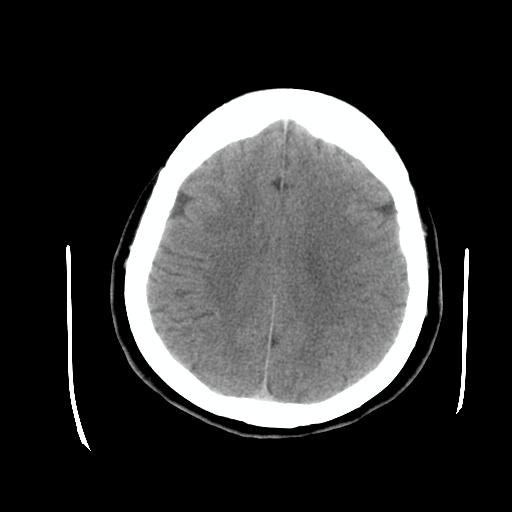

比较下

脉络丛囊肿属神经上皮性囊肿.好发于双侧脉络膜球,通常于影像检查或活检时偶然发现.患者无症状,病灶较小,双侧对称性,脑室膨胀轻.多数病灶在信号上与室管膜囊肿有所不同.在dwi上呈部分高信号,t2 flair上呈不均匀高信号.增强后呈结节状或环形增强

脉络丛囊肿属神经上皮性囊肿.好发于双侧脉络膜球,通常于影像检查或活检时偶然发现.患者无症状,病灶较小,双侧对称性,脑室膨胀轻.多数病灶在信号上与室管膜囊肿有所不同.在dwi上呈部分高信号,t2 flair上呈不均匀高信号.增强后呈结节状或环形增强!支持!